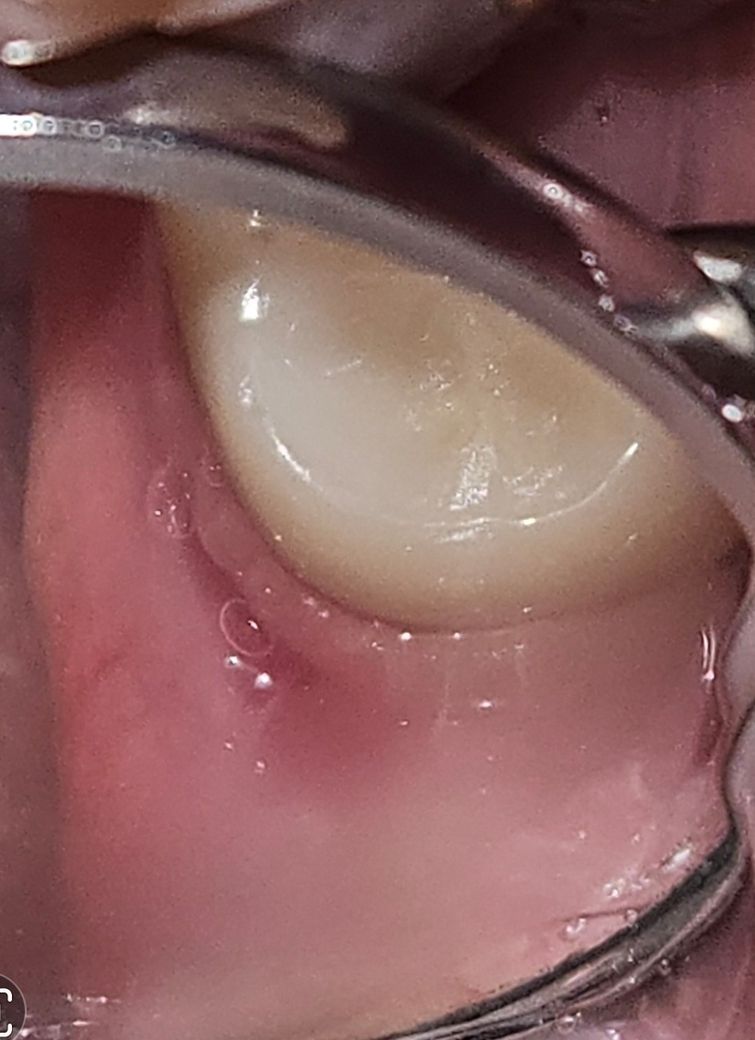

안녕하세요. 맨 뒤 아래 어금니(지르코니아 보철했고 신경은 살아있음. 사랑니는 발치함) 뒷쪽으로 치실을 좀 세게 했었는데 그 때문인건지 잇몸에서 피가나고 붓고 그쪽으로 3일째 욱신한 통증이 있습니다. 맨 안쪽이라 치경으로 어렵게 보았는데 치실로 인한 단순 문제인건지, 잇몸염증이나 다른 문제가 있는건지 궁금합니다.

사진 첨부합니다.

• 사진으로 봤을 경우에는 잇몸에 무리한 자극으로 인해서 잇몸이 헌 것으로 보입니다 해당 부위에 같은 자극을 하지 않는다면 대부분 시간이 지나면서 괜찮아지는 경우가 많습니다

• 대부분은 치실로 인하여 일시적인 잇몸 손상으로 나타나는 증상입니다. 현재 사진으로 보아 큰 문제는 없어 보이며 치실로 인한 잇몸 손상일 가능성이 가장 커 보입니다. 다만 시간이 지나도 통증이나 불편감이 줄어들지 않는다면 치과 방문을 권해드립니다.

• 치실이 자극원이 되었을 수도 있으나 잇몸에 약간 염증으로 인한 부종이 있는 상태입니다. 스케일링 정기적으로 받으시면서 꾸준한 관리가 필요할 것 같습니다. 맨 뒤 어금니 뒷부분은 굳이 치실로 관리할 필요는 없고 양치질 시 칫솔로 꼼꼼히 닦아주면 됩니다.